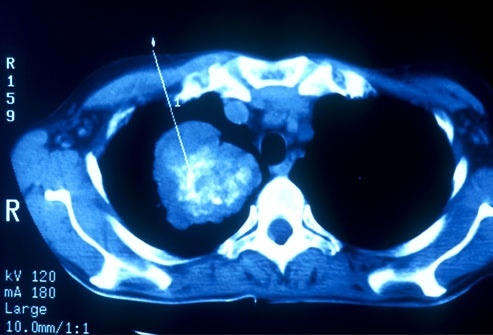

Ung thư phổi có thể được phát hiện sớm bằng chụp CT. Ở Mỹ, có một số đối tượng được khuyên đi sàng lọc ung thư phổi như những người hút thuốc hay có người thân nghiện thuốc, sống trong môi trường ô nhiễm, những người từ 55 đến 80 tuổi được khuyến cáo đi sàng lọc ung thư phổi. Nếu bệnh nhân có tiền sử hút thuốc lá nên định kỳ đi kiểm tra sức khỏe phổi. Ở những người trẻ nếu dừng hút thuốc trong vòng 15 năm có thể ngừng khám sàng lọc ung thư phổi.

Chẩn đoán ung thư phổi

Trong hầu hết các trường hợp, khi bác sĩ nghi ngờ bệnh nhân mắc ung thư phổi với các triệu chứng điển hình như ho mãn tính hoặc thở khò khè, lúc đó, bác sĩ sẽ cho người bệnh đi chụp X-quang hoặc các xét nghiệm hình ảnh khác. Bệnh nhân cũng có thể được yêu cầu xét nghiệm đờm. Nếu một trong các xét nghiệm cho thấy xuất hiện dấu hiệu của ung thư, bước tiếp theo bác sĩ sẽ tiến hành sinh thiết phổi.